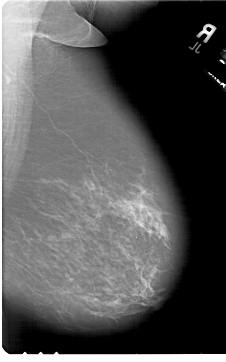

A_1821_1.LEFT_CC

LEFT_CC LINES 6871 PIXELS_PER_LINE 4501 BITS_PER_PIXEL 12 RESOLUTION 43.5 OVERLAY

FILE: A_1821_1.LEFT_CC.OVERLAY

TOTAL_ABNORMALITIES 1

ABNORMALITY 1

LESION_TYPE MASS SHAPE IRREGULAR MARGINS SPICULATED

ASSESSMENT 5

SUBTLETY 5

PATHOLOGY MALIGNANT

TOTAL_OUTLINES 2

BOUNDARY

CORE